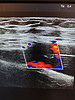

Так, одна из пациенток поликлиники №2 на протяжении многих лет наблюдалась у кардиолога из-за гипертонической болезни, ожирения и сахарного диабета 2 типа. Ей была успешно проведена радиочастотная абляция рецидивирующей формы фибрилляций предсердий. Через какое-то время у женщины появились новые симптомы – варикозное расширение вен и боли в правой голени. Врач-хирург направил пациентку на допплеровское исследование артерий и вен нижних конечностей.

Ирина Ковальчук сумела выявить причину неприятных симптомов. Оказалось, что у женщины образовалась артерио-венозная фистула – аномальное соединение между артерией и веной, которое нарушает кровообращение, может привести к образованию тромбов и сердечной недостаточности.

– Благодаря своевременному выявлению фистулы пациентка была направлена к ангиохирургу. Диагноз был подтвержден, назначено лечение, – подчеркнула заведующая отделением функциональной и ультразвуковой диагностики. – Пациентка находится на диспансерном наблюдении и чувствует себя удовлетворительно. Врачи отмечают положительную динамику: размеры артерио-венозной фистулы уменьшились, что улучшило прогноз заболевания.

фистула 2